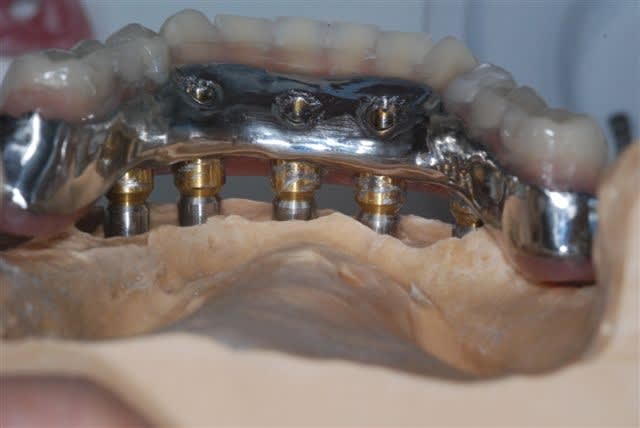

Alors voilà: empreinte pick-up mixte (silicone et plâtre snowhite), RIM avec cire calée sur des piliers hauts, et aujourd'hui retrait des implants provisoire et vissage de la prothèse.

il se trouve que la parallélisme des implants était tel que j'ai pu me passer des piliers multi. L'empreinte au plâtre est sortie sans forcer et l'insertion ce matin à la pose s'est faite de même (je pensais à l'extrême limite devoir shorter un peu les bords des hexagones, mais même pas), juste au dessus des hexagones on a une liaison conique à 11°. Une prothèse est déjà réalisée tout en résine et incluant les piliers usinés, puis la résine est évidée en lingual, une maquette en cire est réalisée en épousant le plus possible les piliers. Elles est ensuite coulée, adaptée contre les piliers et enfin soudée au laser avec apport de cobalt conte les piliers....la passivité est conservée. Maintenant, c'est la première fois que je n'utilise pas les piliers multi, ici c'est assez par hasard que les implants aient été parallèles. c'est vrai que le coût en a été moindre mais ce n'était pas l'objectif premier.

une vue de l'armature lors de la finition au labo